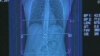

Ông Bettcher nói những bằng chứng từ các nước như Trung Quốc và Pháp cho thấy giá cao hơn cho những sản phẩm thuốc lá dẫn đến sự sụt giảm số người hút thuốc lá và những trường hợp tử vong do thuốc lá gây ra, như ung thư phổi.

Tổ chức Y tế Thế giới báo cáo khoảng sáu triệu người, hầu hết ở những nước đang phát triển, chết sớm vì những bệnh liên quan đến thuốc lá mỗi năm. Con số là nhiều hơn tất cả những trường hợp tử vong do HIV-AIDS, lao và sốt rét cộng lại.